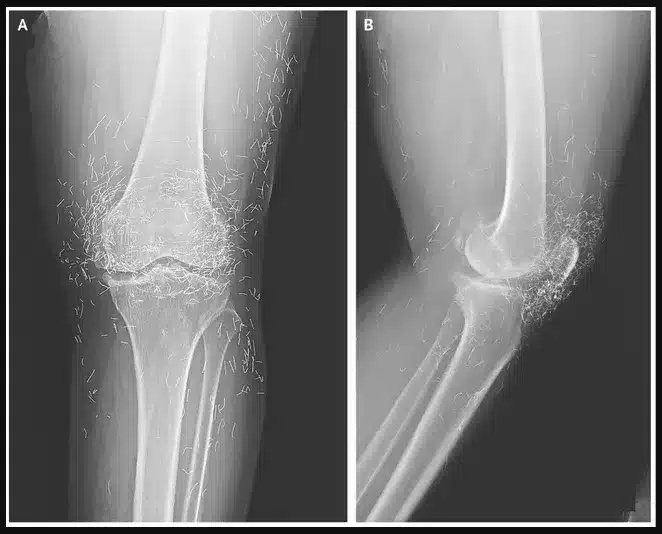

Doctors were recently surprised by an X-ray image of a 65-year-old woman’s knees. The scan showed not just bone, but hundreds of tiny gold needles embedded deep within the tissue. The woman, from South Korea, had been suffering from osteoarthritis, a painful condition where the joints wear down. When traditional pain medications failed to help and caused stomach issues, she turned to an alternative treatment: acupuncture.

In this specific case, her acupuncturist had used gold needles and intentionally left them inside her knees. The goal of this unusual method was to provide continuous stimulation to the joints in an attempt to relieve her chronic pain. While this practice is known in some parts of the world, it is highly unusual and caught her new doctors off guard. Medical experts not involved in her care have pointed out the significant risks of leaving any foreign object inside the body long-term.

These risks include the potential for inflammation, infection, and the formation of painful abscesses. The needles can also interfere with important medical scans, potentially blocking the view of anatomy on an X-ray. Furthermore, a patient with metal needles inside them cannot safely undergo an MRI scan, as the powerful magnets could cause the needles to move, potentially damaging blood vessels or tissue. While acupuncture remains a popular treatment for joint pain, there is limited scientific evidence to prove its effectiveness, and this extreme version of the practice highlights the potential dangers of alternative therapies.